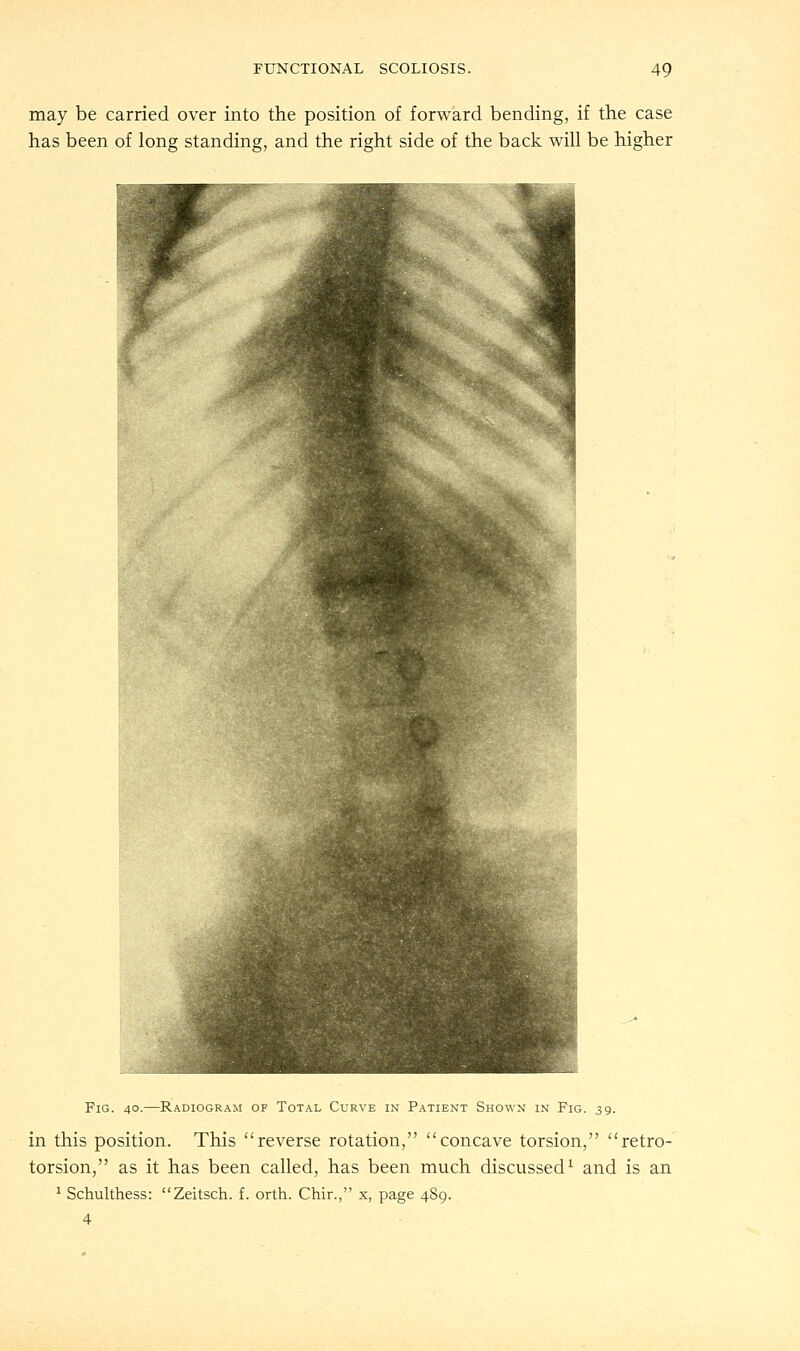

67/214 page 49